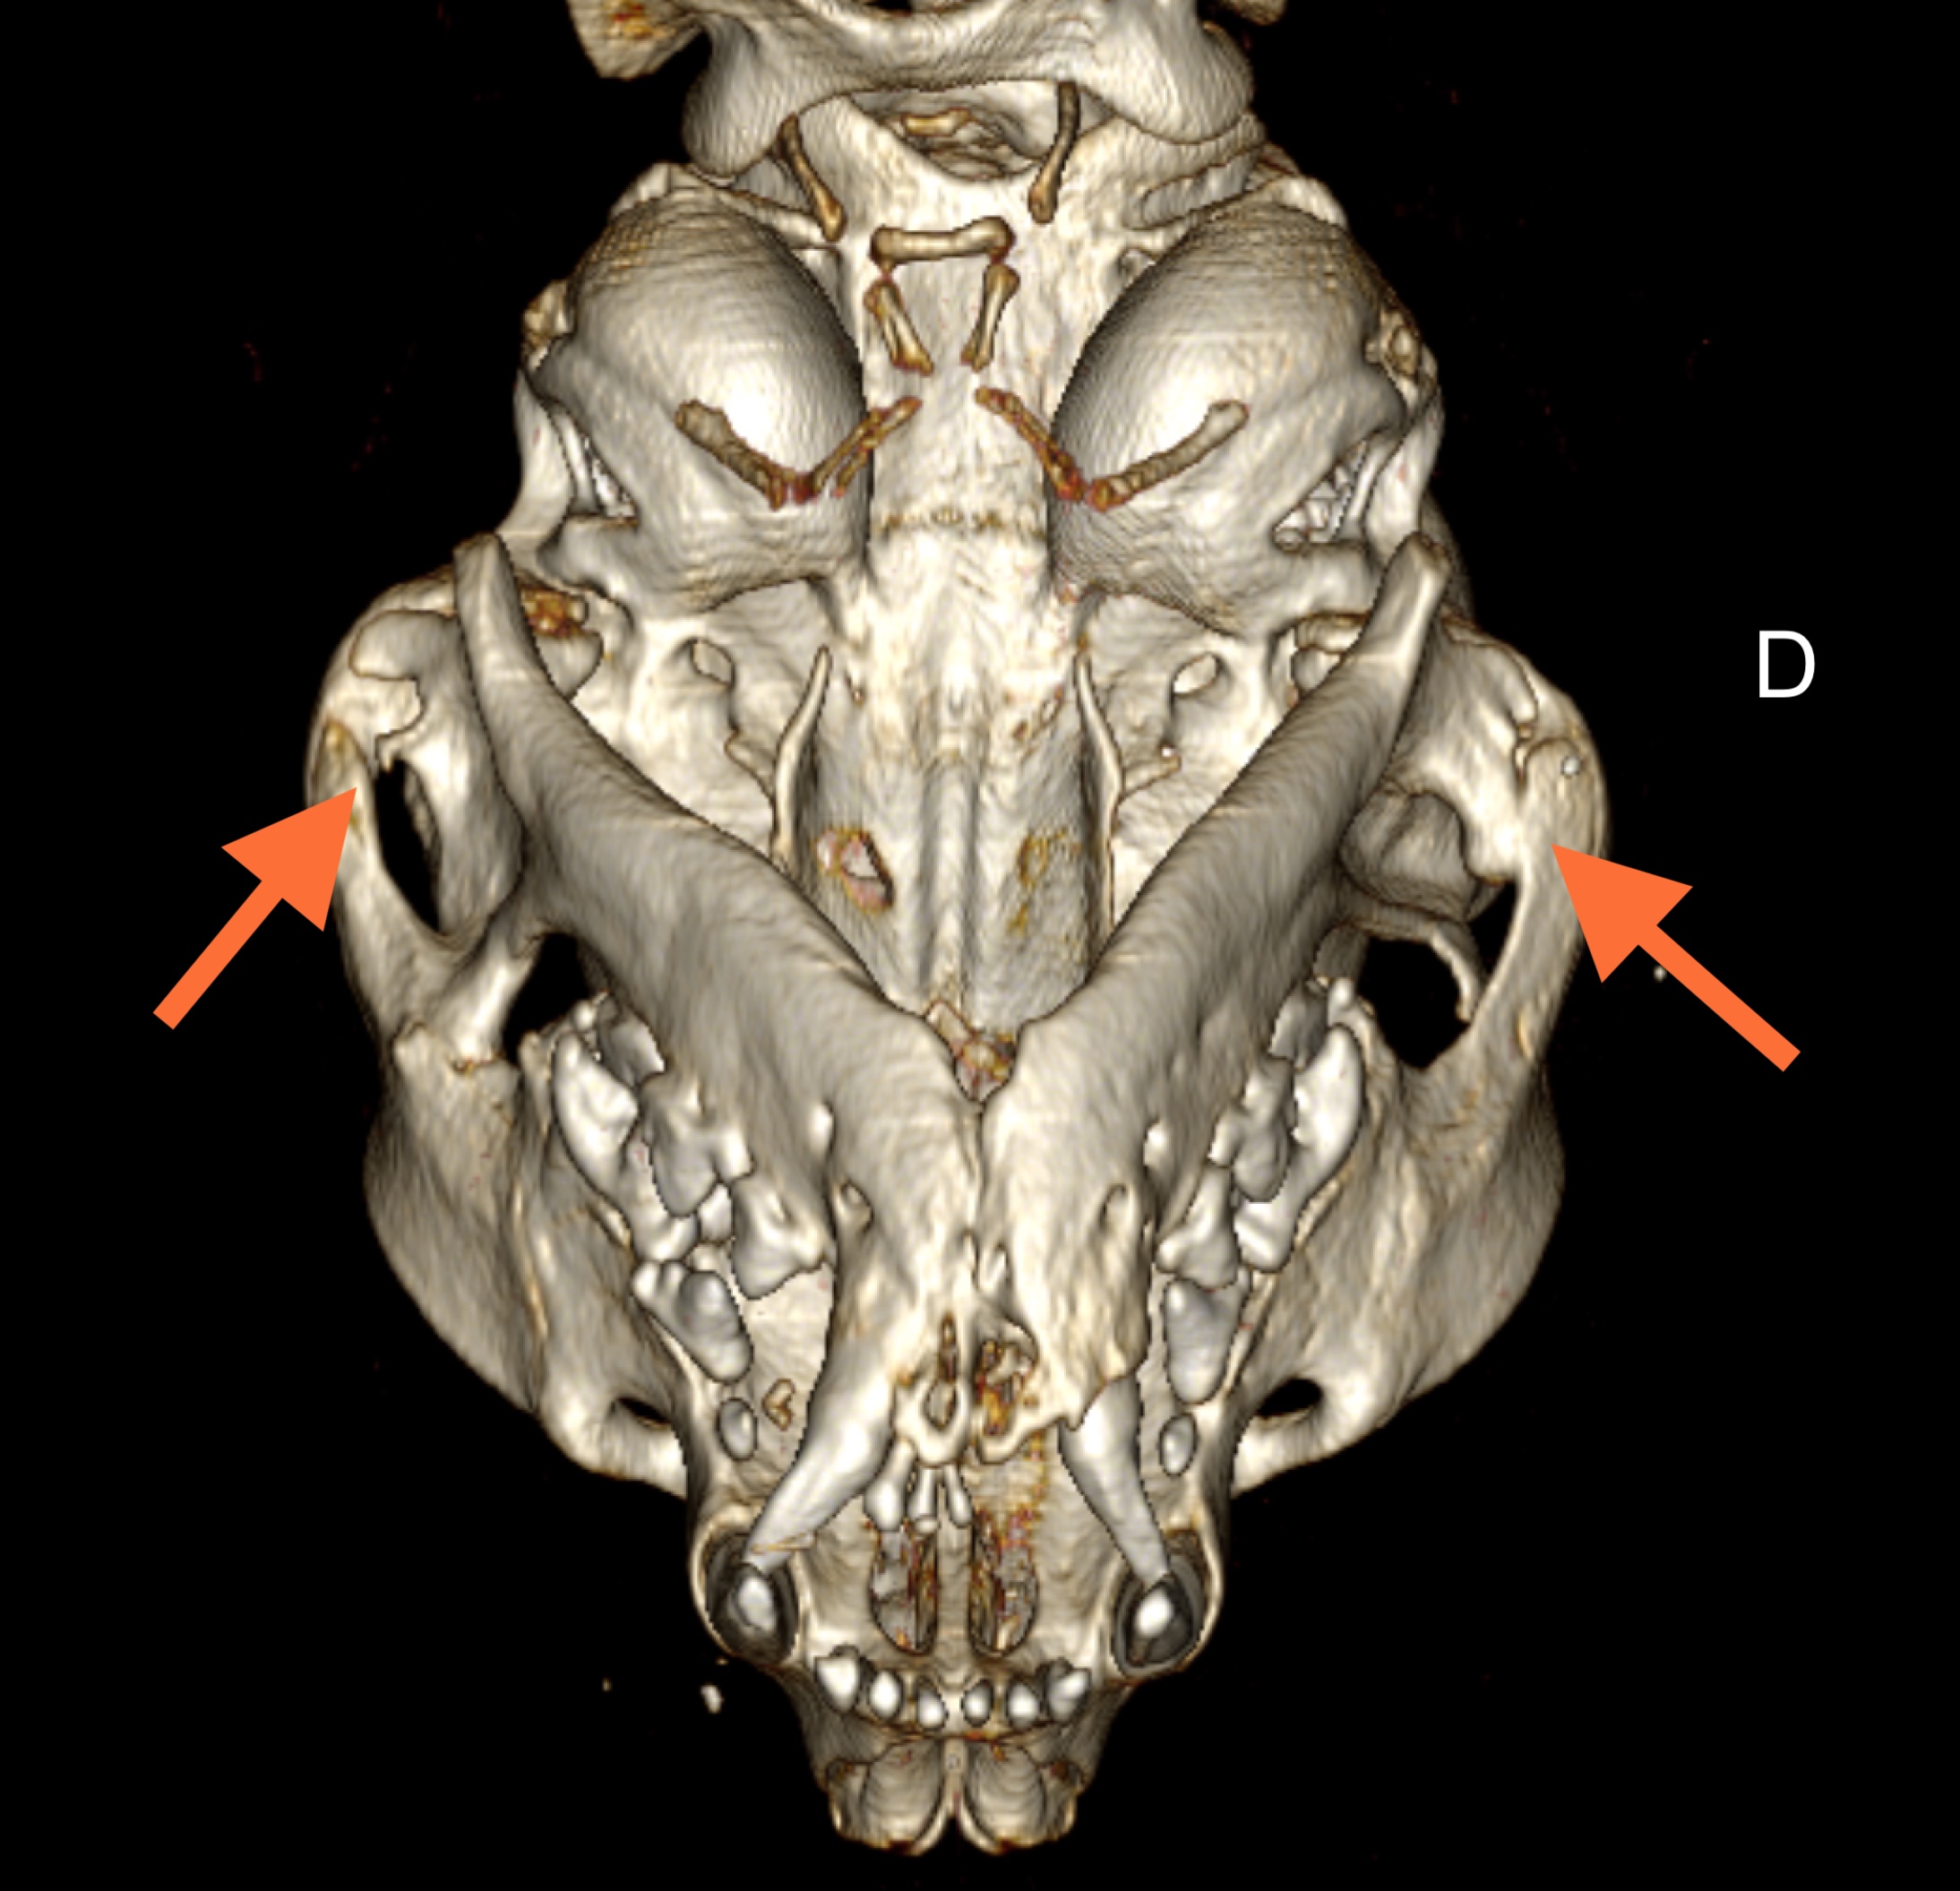

Un examen tomodensitométrique est réalisé afin de visualiser les lésions en trois dimensions et faciliter la prise en charge chirurgicale. Des remaniements sévères des branches montantes des mandibules qui apparaissent épaissies et déviées caudalement sont mis en évidence. A gauche, un pontage osseux complet est observé entre le bord crânial de la branche montante de la mandibule et le processus temporal de l’os zygomatique, de même le bord caudal de la branche montante de la mandibule forme un pont osseux incomplet avec le processus zygomatique de l’os temporal gauche. A droite, un éperon osseux se détache également du bord crânial de la branche mandibulaire en direction de l’arcade zygomatique droite et le bord caudal de la branche montante de la mandibule droite forme un pont osseux complet avec le processus zygomatique de l’os temporal droit. Les articulations temporo-mandibulaires restent symétriques. Une malocclusion dentaire est également visualisée secondaire à une déviation modérée à droite de la mandibule.

Pseudo-ankylose bilatérale des ATM.